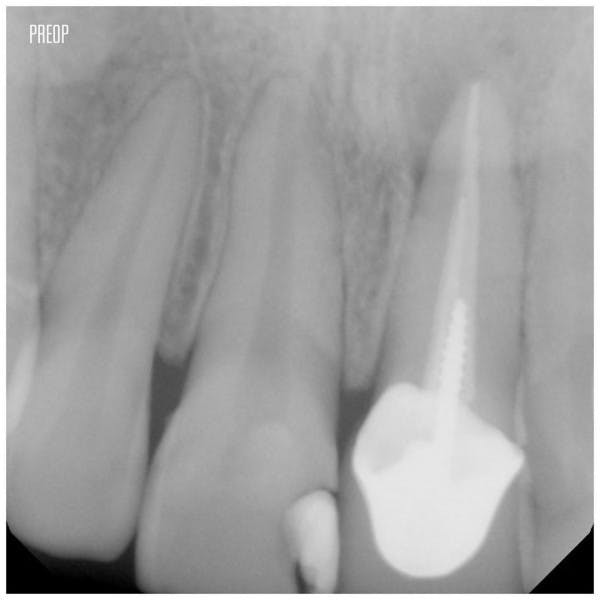

歯根のう胞 歯根嚢胞 スーパー根管治療 症例その1 小机歯科 神奈川県横浜市の歯医者